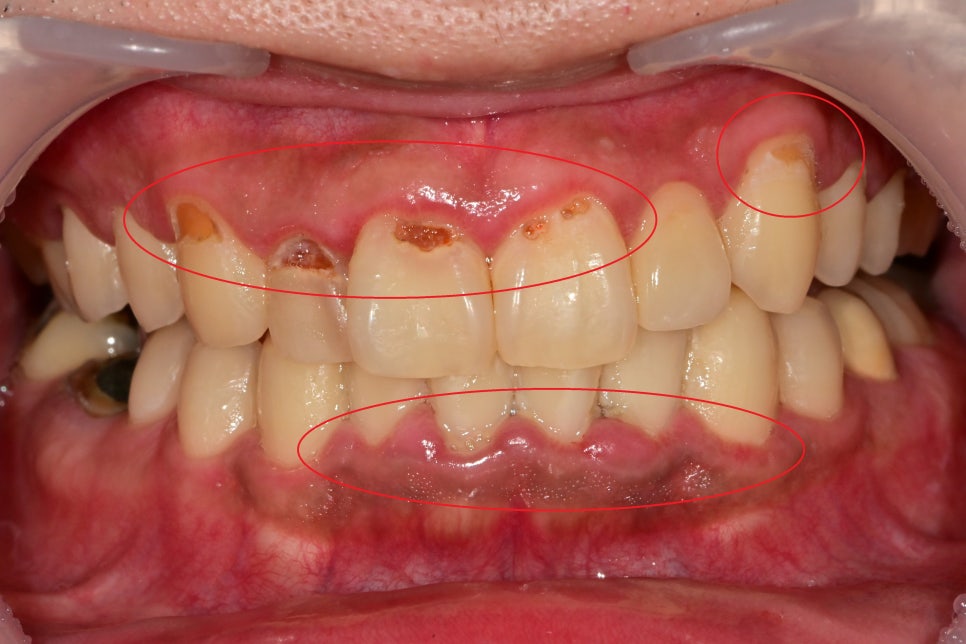

치아와 잇몸 경계부에 플라그(치태)가 쌓이게 되면서

제거가 잘 안되다 보니 주변 잇몸이 빨갛게 붓고

다발성 충치가 유발된 상태였습니다.

앞니 쪽은 양치하기가 쉽다고 생각을 하기 때문에

종종 앞니 쪽 잇솔질을 빠르게 넘어가는 일이 생깁니다.

대부분 놓치는 부분이 잇몸과 치아의 경계 부위, 치아 사이입니다.